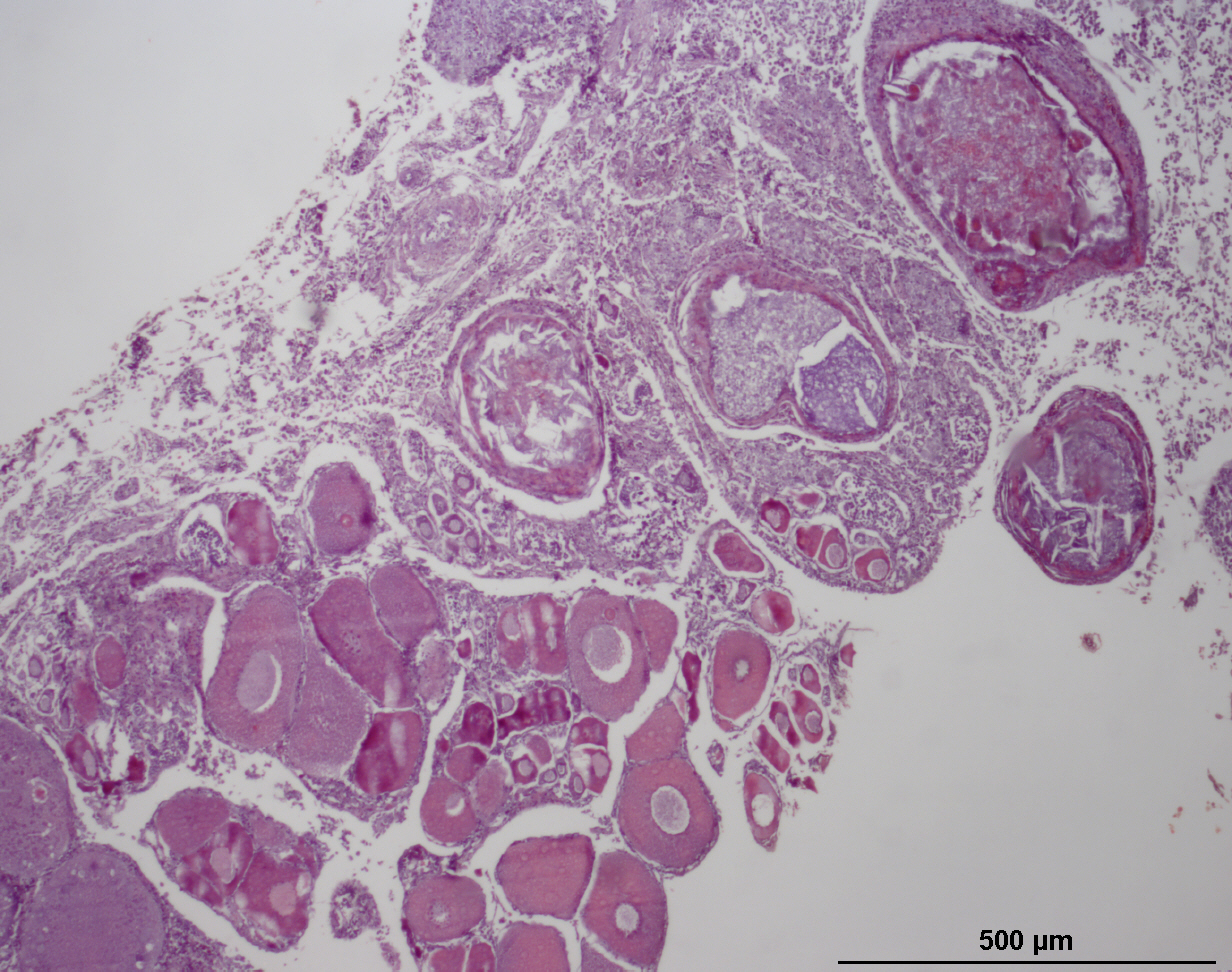

Rutilus rutilus

Roach (inc. hybrids)

Intersex

Testis

Small to large previtellogenic oocytes distributed throughout the testicular tissue.